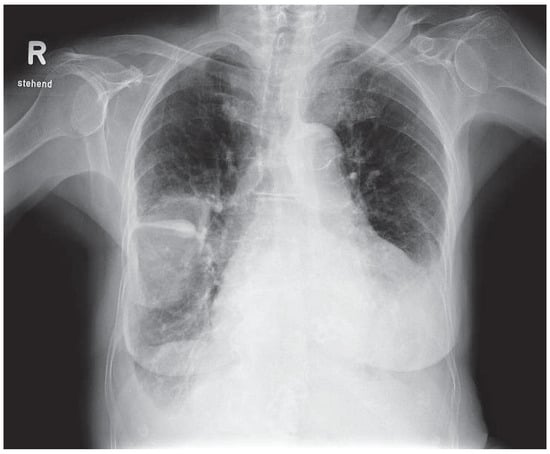

Case report. A 63-year-old hypertensive male presented with atypical chest discomfort and breathlessness on exertion [...]